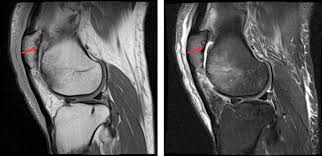

Medial Femoral Condyle Chondromalacia : Chondromalazie Stockfotos Und Bilder Kaufen Alamy, Can chondromalacia patellae be cured by conservative treatment avoiding surgery?. Osteonecrosis, or bone death, of the medial femoral condyle is treated either through nonsurgical or surgical methods, the hospital for special surgery explains. Pattern typical of grade i chondromalacia. The optimum location for the fam portal during acl reconstruction should avoid cartilage damage to the medial femoral condyle. The purpose of this trial is to evaluate the safety and effectiveness of the biphasic cartilage repair implant (bicri) compared to marrow stimulation in the treatment of chondral and osteochondral lesions located on the medial femoral condyle, lateral femoral condyle, or trochlea of the knee. Although extensive marrow edema is present, there is only mild to moderate chondromalacia at the medial femoral condyle, and no meniscal tear.

Femoral condyle and talus were selected. Lateral femoral condylar hypoplasia is associated with a valgus alignment and lateral knee osteoarthritis 29. 12 tegner y, lysholm j. Moving the insertion of the quadriceps tendon medially at the tibial. .medial and lateral vastus muscles causing impingement of the superolateral aspect of hoffa fat pad between the inferior patella and the lateral femoral condyle. The purpose of this trial is to evaluate the safety and effectiveness of the biphasic cartilage repair implant (bicri) compared to marrow stimulation in the treatment of chondral and osteochondral lesions located on the medial femoral condyle, lateral femoral condyle, or trochlea of the knee. Contusion of the lateral femoral condyle and small knee effusion. Find specific details on this topic and related topics from the msd vet manual. Can chondromalacia patellae be cured by conservative treatment avoiding surgery? Mri can be helpful in detecting articular cartilage injuries, chondromalacia patellae, patellar stress fractures, and loose bodies. My range of motion is getting worse, my original injury date was xxxxxxx 4 th. Frequently, there are no localizing signs, although mild effusion of the medial femorotibial and/or femoropatellar joints may be evident. The etiology of chondromalacia patellae.

Moving the insertion of the quadriceps tendon medially at the tibial. Although extensive marrow edema is present, there is only mild to moderate chondromalacia at the medial femoral condyle, and no meniscal tear. Find specific details on this topic and related topics from the msd vet manual. Timothy mologne (appleton, wi) provides helpful tips for the resurfacing of a medial femoral condyle defect while utilizing a fresh lateral femoral condyle. Of the upper medial femoral condyle (same as for the talus.